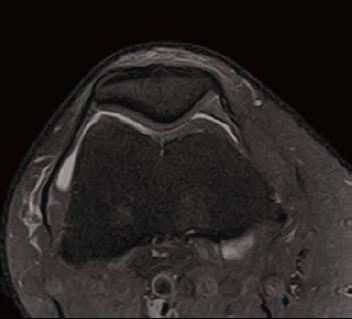

Випадок 2. Коліно високої роздільної здатності

Чоловік 26 років проходить посттравматичну діагностику, є скарга на біль.

• Відсутність травматичного пошкодження.

Рис. 7 Co FSE PD FS, товщина зрізу 3 мм,

роздільна здатність 0,2 мм.